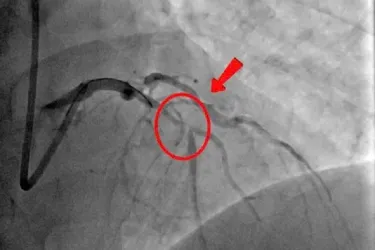

Tại thời điểm nhập viện, bệnh nhân kích thích, vật vã, tím môi, phù mặt - cổ, nổi vân tím toàn thân, khó thở liên tục, phổi giảm thông khí, mạch quay không bắt được, mạch bẹn nhanh nhỏ. Trên người có hơn 150 vết ong đốt chi chít, đỏ sẫm, phồng rộp gây đau nhức dữ dội.

Ngay lập tức, ê-kíp thầy thuốc Khoa Cấp cứu nhận định đây là trường hợp sốc phản vệ độ 3 - mức độ nặng, có thể đe dọa tính mạng nếu không xử trí nhanh. Bệnh nhân được khẩn cấp điều trị theo đúng phác đồ: tiêm Adrenaline, thở oxy, truyền dịch, theo dõi sát các chỉ số sinh tồn.

Sau can thiệp, tình trạng bệnh nhân cải thiện rõ: tỉnh táo, tiếp xúc tốt, hết tím môi, đỡ đau đầu và thở nhẹ. Bệnh nhân sau đó được chuyển tuyến trên để tiếp tục theo dõi và điều trị chống độc, kiểm soát tổn thương đa cơ quan do nọc độc ong gây ra.